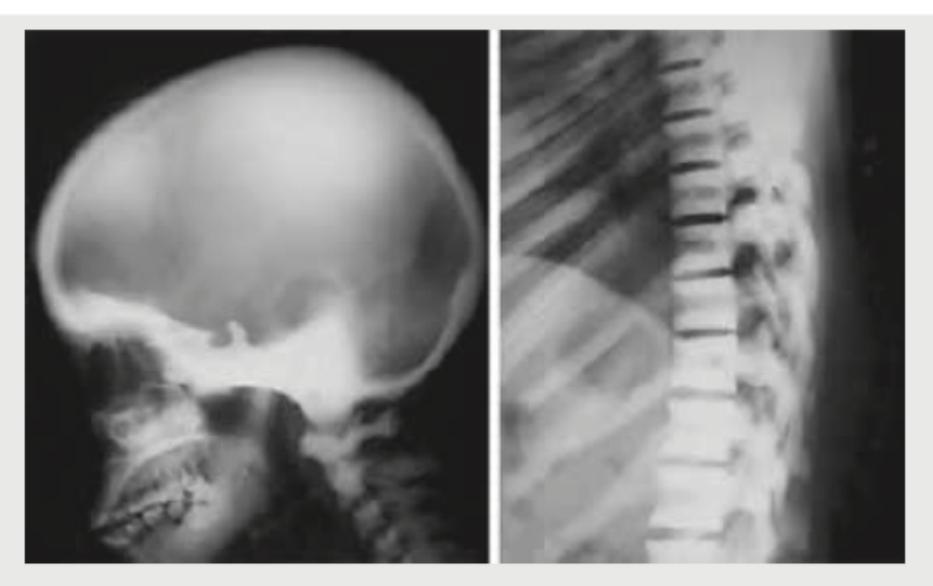

Comment on the diagnosis based on the skull and vertebral changes shown in the radiological image below:

Explanation: ***Thalassemia*** - The skull X-ray shows prominent **"hair-on-end" appearance** due to widening of the diploic space and thinning of the outer table, characteristic of chronic erythroid hyperplasia in thalassemia. - The vertebral bodies show a **"fishmouth" or "codfish" deformity**, a sign of severe osteopenia and bone marrow expansion commonly seen in thalassemia. *Rickets* - Rickets primarily affects the **growth plates** in children, leading to wide, irregular growth plates, cupping, and fraying of metaphyses, which are not seen here. - While it causes bone softening, the specific cranial and vertebral changes observed, like **"hair-on-end"** or "fishmouth" vertebrae, are not typical of rickets. *Osteopetrosis* - Osteopetrosis is characterized by **increased bone density** (sclerotic bones) due to defective osteoclast function, leading to abnormally thick and dense bones. - The radiographs show **osteopenia** and bone marrow expansion, which is the opposite of what is seen in osteopetrosis. *Hyperparathyroidism* - Hyperparathyroidism typically causes **subperiosteal bone resorption**, especially in the phalanges, and sometimes **brown tumors**. - While it can lead to generalized osteopenia, the specific "hair-on-end" skull and "fishmouth" vertebrae are not hallmark features; **salt-and-pepper skull** may be present, which differs from the findings here.